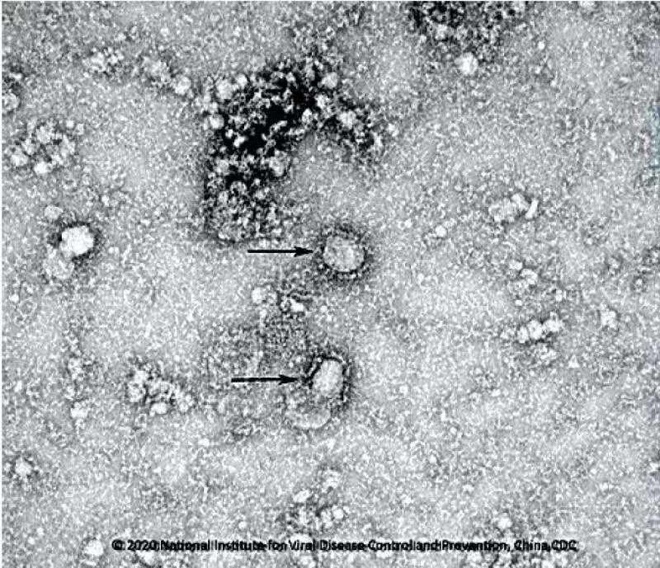

Loại thuốc xịt diệt khuẩn mới được phát triển để sử dụng tại Trung tâm Y tế lâm sàng công cộng thành phố Thượng Hải, nhằm bảo vệ các nhân viên khỏi virus corona.

Loại thuốc mới này được phát triển bởi nhóm các nhà khoa học của Viện Nghiên cứu các dịch bệnh mới tại Trung tâm Y tế lâm sàng công cộng thành phố Thượng Hải. Theo Xu Jianqing, người đứng đầu viện nghiên cứu, nhóm của ông đã dành hơn 6 năm để phát triển loại thuốc mới để điều trị các bệnh truyền nhiễm ở đường hô hấp. Hiện thuốc đã được chứng minh hiệu quả trên động vật, đạt tiêu chí sử dụng lâm sàng.

Thuốc đã được chứng minh có hiệu quả chống lại virus corona, đóng vai trò tích cực trong điều trị nhiễm trùng giai đoạn đầu. Tuy nhiên, thuốc vẫn chưa được phê duyệt lưu hành và sản xuất trên thị trường. Do đó, nó không được phép sử dụng hợp pháp trong việc điều trị cho bệnh nhân. Hiện nó mới chỉ được sử dụng cho nhân viên y tế tại Trung tâm y tế lâm sàng công cộng thành phố Thượng Hải.

Thuốc xịt mới chứa 2 hoạt chất, một chất kiềm chế sự nhân đôi của virus, chất còn lại kiểm soát quá trình virus gây bệnh ở người. Ông Jianqing giải thích virus khiến con người mắc bệnh bằng cách gây viêm. Các thành phần thuốc mới có thể ức chế viêm và sửa chữa niêm mạc đường hô hấp.